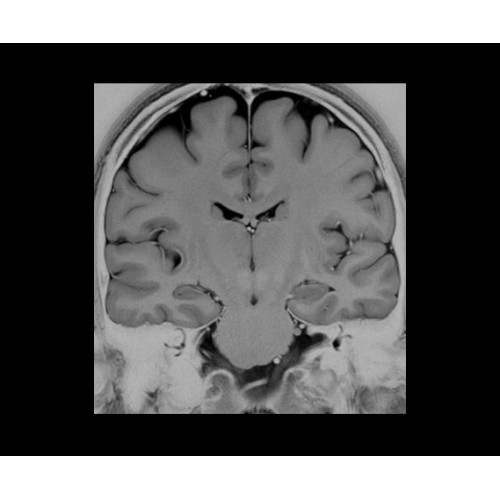

SIGNA PET/MR 3.0T — это гибридная система, в которой совмещаются две принципиально разные технологии — магнитно-резонансную томографию (МРТ) и позитронно-эмиссионную томографию (ПЭТ). Система отличающийся высокой чувствительностью и эффективностью и предназначена для диагностики в области онкологии, неврологии, кардио-васкулярных исследований, исследований воспалительных процессов.

Компания GE Healthcare представляет революционную, полностью интегрированную систему SIGNA PET/MR1, в которой сочетаются времяпролетная технология (TOF) и возможности напряженности магнитного поля 3.0 Тл. Мы поможем вам поднять исследования на более высокий уровень. SIGNA PET/MR позволяет достичь впечатляющей точности и скорости исследований, а благодаря новейшей технологии реконструкции Q.Clear2 качество изображений улучшается в два раза. Кроме того, в систему включен полный набор клинических приложений и гибких катушек для проведения любых видов исследования, открывая для вас возможности визуализации, о которых вы даже не догадывались.

Впечатляющие клинические возможности

Система SIGNA PET/MR предлагает впечатляющие клинические возможности и открывает доступ к наиболее полным пакетам программных приложений.

• Специальный пакет приложений для измерения и сравнения объемных изображений ЦНС с нормами поможет вам в диагностике нейродегенеративных заболеваний, а дополнительные инструменты визуализации — в постановке точного диагноза с помощью бета-амилоидов и радиоизотопных маркеров ФДГ.